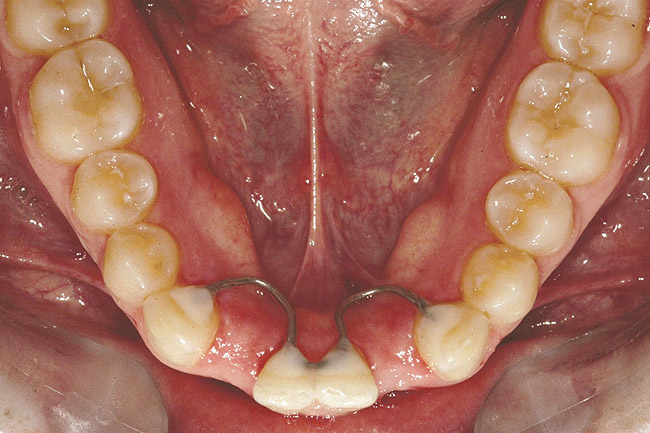

Fig 11. Corticotomy SFOT. A 42-year-old male presented with a history of extraction orthodontic therapy.

Figure 11

Fig 12 (and Fig 13). Incisors were too upright and had severe incisal wear. He was concerned about esthetics of the worn teeth and his insufficient lip support. Progress photo and panorex 9 months after corticotomies were performed on Nos. 6 through 11. Previous extraction sites were reopened orthodontically to improve function and fill lip support. Incisal edges were restored provisionally with composite resin. Note that despite the creation of adequate spaces to replace missing teeth, there is inadequate room for placement of dental implants because of severe tipping of all the anterior teeth. Osteotomy SFOT may have been a better choice because it would have allowed needed alveoloskeletal correction (without excessive tipping) instead of the primarily dentoalveolar correction common in corticotomy SFOT. Restorative dentist: Brad Jones, DDS.

Fig 13 (and Fig 12). Incisors were too upright and had severe incisal wear. He was concerned about esthetics of the worn teeth and his insufficient lip support. Progress photo and panorex 9 months after corticotomies were performed on Nos. 6 through 11.